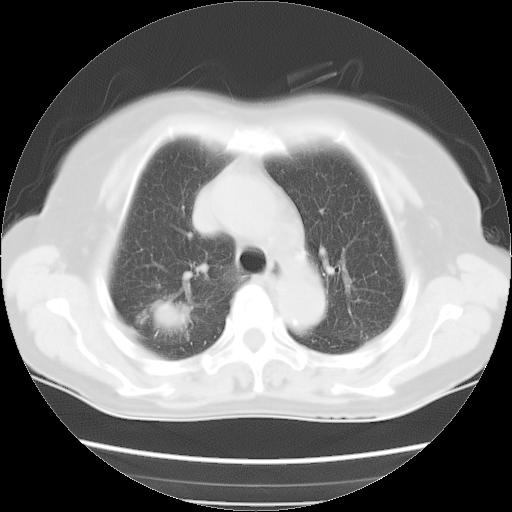

以下是引用夏季在2007-9-18 11:00:00的发言:[br]1。右肺肿块,周围有短毛刺,肺门侧有血管与其相连,胸壁侧有胸膜凹陷征,考虑周围性肺癌 2。左侧甲状腺软组织肿块,内有高密度钙化灶,考虑左侧甲状腺腺瘤。

以下是引用卜一在2007-9-18 14:41:00的发言:[br]右肺肿块:毛刺+胸膜凹陷征+供血血管+浅分叶+强化。支持:周围性肺癌 !另:左侧甲状腺腺瘤!